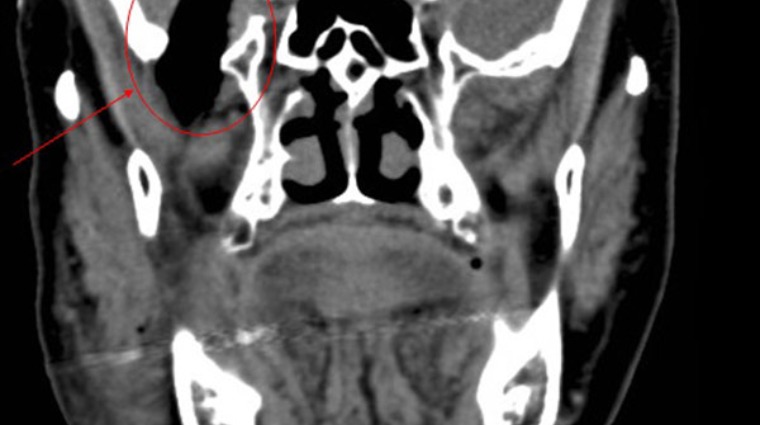

▲74歲陳姓婦人因跌倒導致玉米莖插入顱內,所幸經開顱手術後重建頭骨,並未留下後遺症。

收治陳女士的國泰綜合醫院神經外科張明元醫師指出,玉米莖從陳女士臉部右顴骨下方一路刺破顱底,造成臉部3公分傷口及顱底破裂,加上她患有心肌梗塞,心臟裝有5支血管支架,長期服用抗凝血藥,增加手術麻醉困難度。

經開顱手術先截斷玉米莖,分別取出3公分及5公分,合計共8公分玉米莖,再進行顱底重建,費時4-5小時順利完成手術。但腦部因玉米莖殘留的穢物,引發後續感染造成腦膿瘍,只得二次開頭顱拿掉壞死頭骨,之後再利用人工鈦金屬重建頭骨,現已康復出院,且未留下任何後遺症。